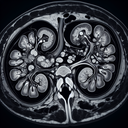

МРТ нирок

Магнітно-резонансна томографія (МРТ) нирок – це неінвазивний метод діагностики, який використовує потужні магнітні поля і радіохвилі для отримання детальних зображень нирок та оточуючих тканин. Цей метод дозволяє виявити різноманітні патології, такі як пухлини, камені в нирках, вади розвитку, а також запальні процеси. Переваги МРТ нирок: - Безпека: не використовує шкідливе рентгенівське випромінювання...